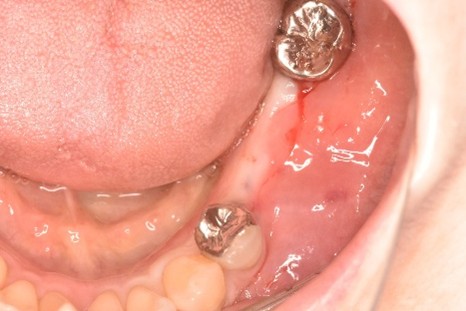

女性Sさん 60代(インプラント)

主訴

左下が腫れていて、噛むと痛い。

治療内容

左下ブリッジの支台になっている大臼歯が、歯根の破折を起こしていましたので、抜歯しました。奥歯3本欠損のところに、2本インプラントを埋入しました。

所感

奥歯3本歯のないところを補う方法は、インプラント、あるいは取り外しの部分入れ歯、という2つの方法があります。部分入れ歯は支台になっている歯に負担がかかるため、問題が起きた時には、支台になっている歯がダメになり、更に抜歯になる可能性が大きいです。最初は3本の欠損から、4本、5本と歯がないところが拡大してしまいます。また、義歯は異物感が大きく慣れるのが大変で、上下自分の歯どうしで噛む感覚と同じようには噛むことができません。

インプラントは、単独で植立し他の歯に負担がかからなく、自分の歯と同じような感覚で食事が出来ます。患者さんは、インプラント治療を選択されました。治療後、「約半年と時間がかかり、緊張の連続でしたが、丁寧に治療してもらいありがとうございました。今日から両側の歯で噛めるので、安心しました。」と、とても喜んでくださいました。

この症例は、3DナビゲーションシステムのX-ガイドを使って埋入しました。X-ガイドは骨の中の神経や血管の位置をリアルタイムに確認しながら手術が実行できるため、より安全で精度の高いインプラント埋入ができます。

インプラント2本:¥363,000×2本=¥726,000(税込)

ポンティック1本(インプラント間をつなぐ部分):¥115,500(税込)

合計:¥841,500(税込)